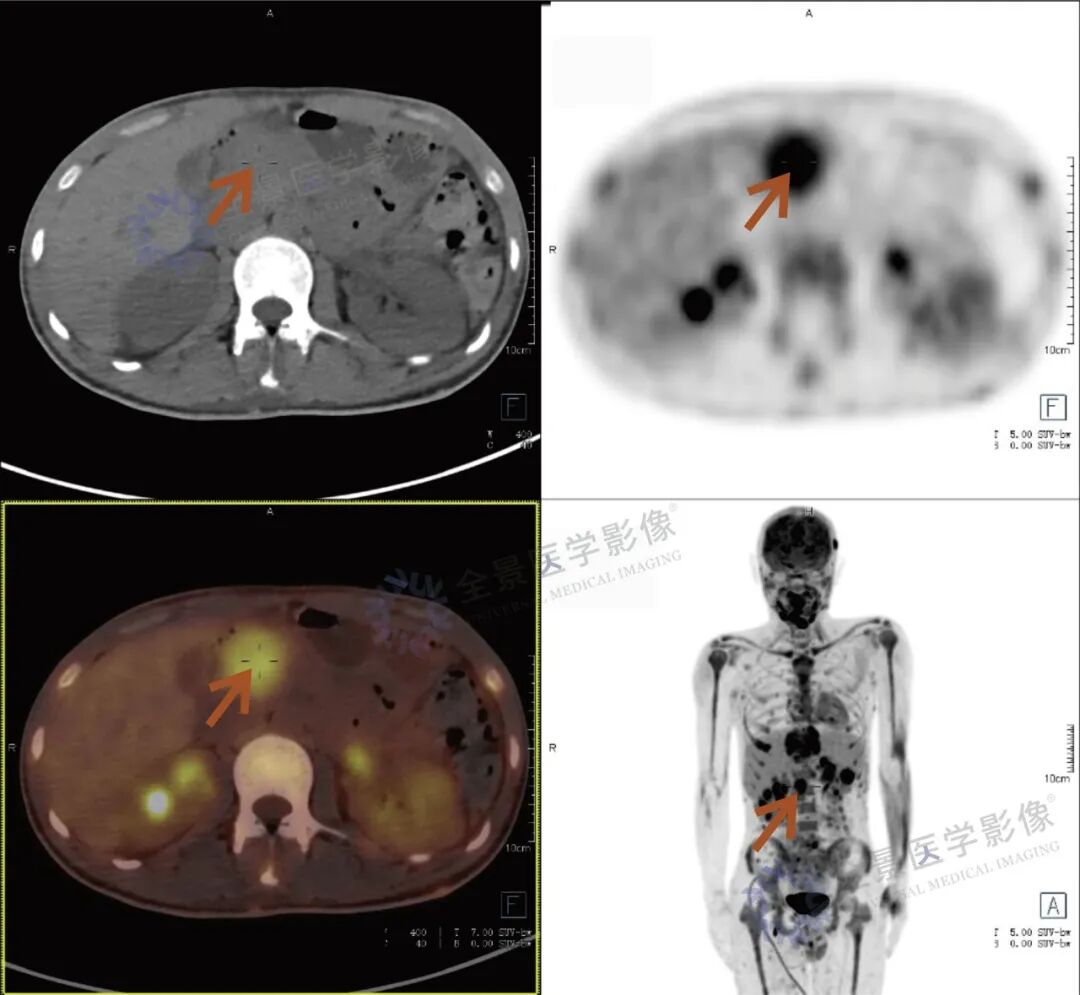

张先生(化名),因持续3个多月的腹痛、腰痛在外院就诊。初始CT检查发现其胸11椎体骨质破坏伴周围软组织肿胀,考虑为“脊柱结核”等感染性病变,并接受了中药治疗。然而,两个月后,张先生又出现了新的症状——牙痛。 经病理活检及免疫组化检查,最终确诊为极为罕见的Erdheim-Chester病。为全面评估这一可累及全身多系统疾病的侵犯范围、明确病灶活动性,并为制定精准治疗方案提供依据,张先生进行了全身PET/CT检查。 PET/CT检查图像: PET/CT检查结果: (1)中轴骨及四肢骨广泛FDG代谢活跃伴信号异常;其中胸10、胸11椎体病灶周围软组织增厚,累及邻近椎管内及双侧椎间孔、双侧胸膜,并与主动脉分界不清。 (2)全身皮下及肌层内多发结节及肿块,FDG代谢活跃;全身软组织广泛肿胀。 (3)鼻咽各壁增厚,顶后壁为著,FDG代谢活跃。 (4)甲状腺多发结节,FDG代谢活跃;双肾及胰腺多发结节及肿块,FDG代谢活跃;双侧阴囊内异常信号伴FDG代谢活跃; (5)左侧锁骨上窝、纵隔内(2L区、3A区)、降主动脉旁、左侧横膈前组、右侧腋窝、左肾周间隙、肠系膜区、双侧髂血管旁多发淋巴结,FDG代谢活跃; (6)心包局部呈结节状稍增厚,FDG代谢轻度活跃; 综上,结合临床,均考虑Erdheim-Chester病所致。 此次PET/CT不仅证实了已知的脊柱病变,更一次性揭示了临床尚未怀疑的、广泛存在于内脏、淋巴结及软组织的隐匿病灶,为疾病分期与治疗提供了决定性依据。